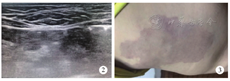

图2

右腰部淋巴管瘤硬化治疗后1个月复查,B超检查提示病灶基本消退

图3

右髂腰部鲜红斑痣,经8次激光治疗后颜色明显较前变淡

Fig 2

B-ultrsonography showed that the lymphangioma on the right waist basically disappeared after sclerotherapy.

Fig 3

After 8 times of laser treatment, the color of port wine stains on the right waist was obviously lighter than before.